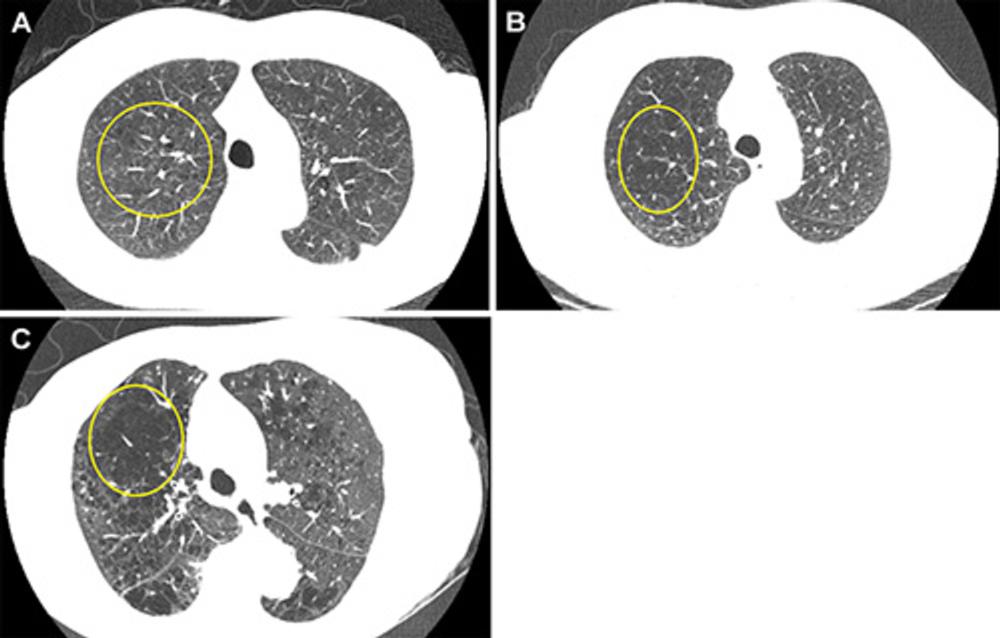

Figure 1. Representative axial images of mild, moderate, and severe emphysema at baseline low-dose CT (LDCT). Participants were categorized as having no emphysema or mild, moderate, or severe emphysema. When present, emphysema was mild if no distinct regions of reduced attenuation were visible on the CT scan, but vascular splaying indicates parenchymal expansion, or if only occasional discrete low-attenuation regions were observed. Moderate emphysema was defined by the presence of identifiable low-attenuation regions affecting less than half of the lung parenchyma, whereas severe emphysema was defined by the presence of identifiable low-attenuation regions that involved more than half of the lung parenchyma. A scoring system from 0 to 3 was applied, corresponding to none, mild, moderate, and severe emphysema, respectively. Yellow circle indicates the extent of emphysema. (A) A 67-year-old man with mild emphysema at baseline LDCT in 2002. Baseline LDCT scan shows vascular splaying, suggesting parenchymal expansion due to emphysema and occasional discrete low-attenuation regions. The participant ultimately died of cardiovascular disease 15.4 years (184.2 months) later. (B) A 69-year-old man with moderate emphysema at baseline LDCT in 2007. The participant died of cardiovascular disease 1.8 years (21.9 months) later. Identifiable low-attenuation regions affected less than half of the lung parenchyma. (C) An 85-year-old woman with severe emphysema at baseline LDCT in 2006. After 5.5 years (65.5 months) of follow-up, the participant died due to chronic obstructive pulmonary disease–related causes. Identifiable low-attenuation regions involved more than half of the lung parenchyma.